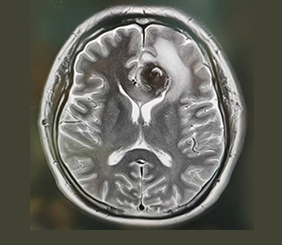

腦血管病診療中心聚集了一批擁有豐富臨床經(jīng)驗(yàn)和深厚學(xué)術(shù)背景的腦血管病專家。中心專注于腦血管疾病的預(yù)防、診斷、治療及康復(fù),主要診治各類腦血管疾病,如顱內(nèi)動(dòng)脈瘤、蛛網(wǎng)膜下腔出血、腦血管畸形、煙霧病、硬腦膜動(dòng)靜脈瘺、顱內(nèi)靜脈系統(tǒng)疾?。ㄈ珈o脈竇血栓、靜脈梗塞引起的腦梗死或腦出血)、外傷或自發(fā)性海綿竇內(nèi)動(dòng)靜脈瘺(CCF)、脊髓內(nèi)血管畸形、髓周動(dòng)靜脈瘺、硬脊膜動(dòng)靜脈瘺、腦和脊髓的海綿狀血管瘤,顱內(nèi)血管狹窄、頸動(dòng)脈狹窄、椎-基底動(dòng)脈狹窄、鎖骨下動(dòng)脈狹窄、顱內(nèi)和頸部的血管夾層、顱內(nèi)或頸部血供豐富的腫瘤術(shù)前栓塞或化療等。從疾病的早期篩查、診斷到治療及后期康復(fù),我們提供全面的診療服務(wù)。